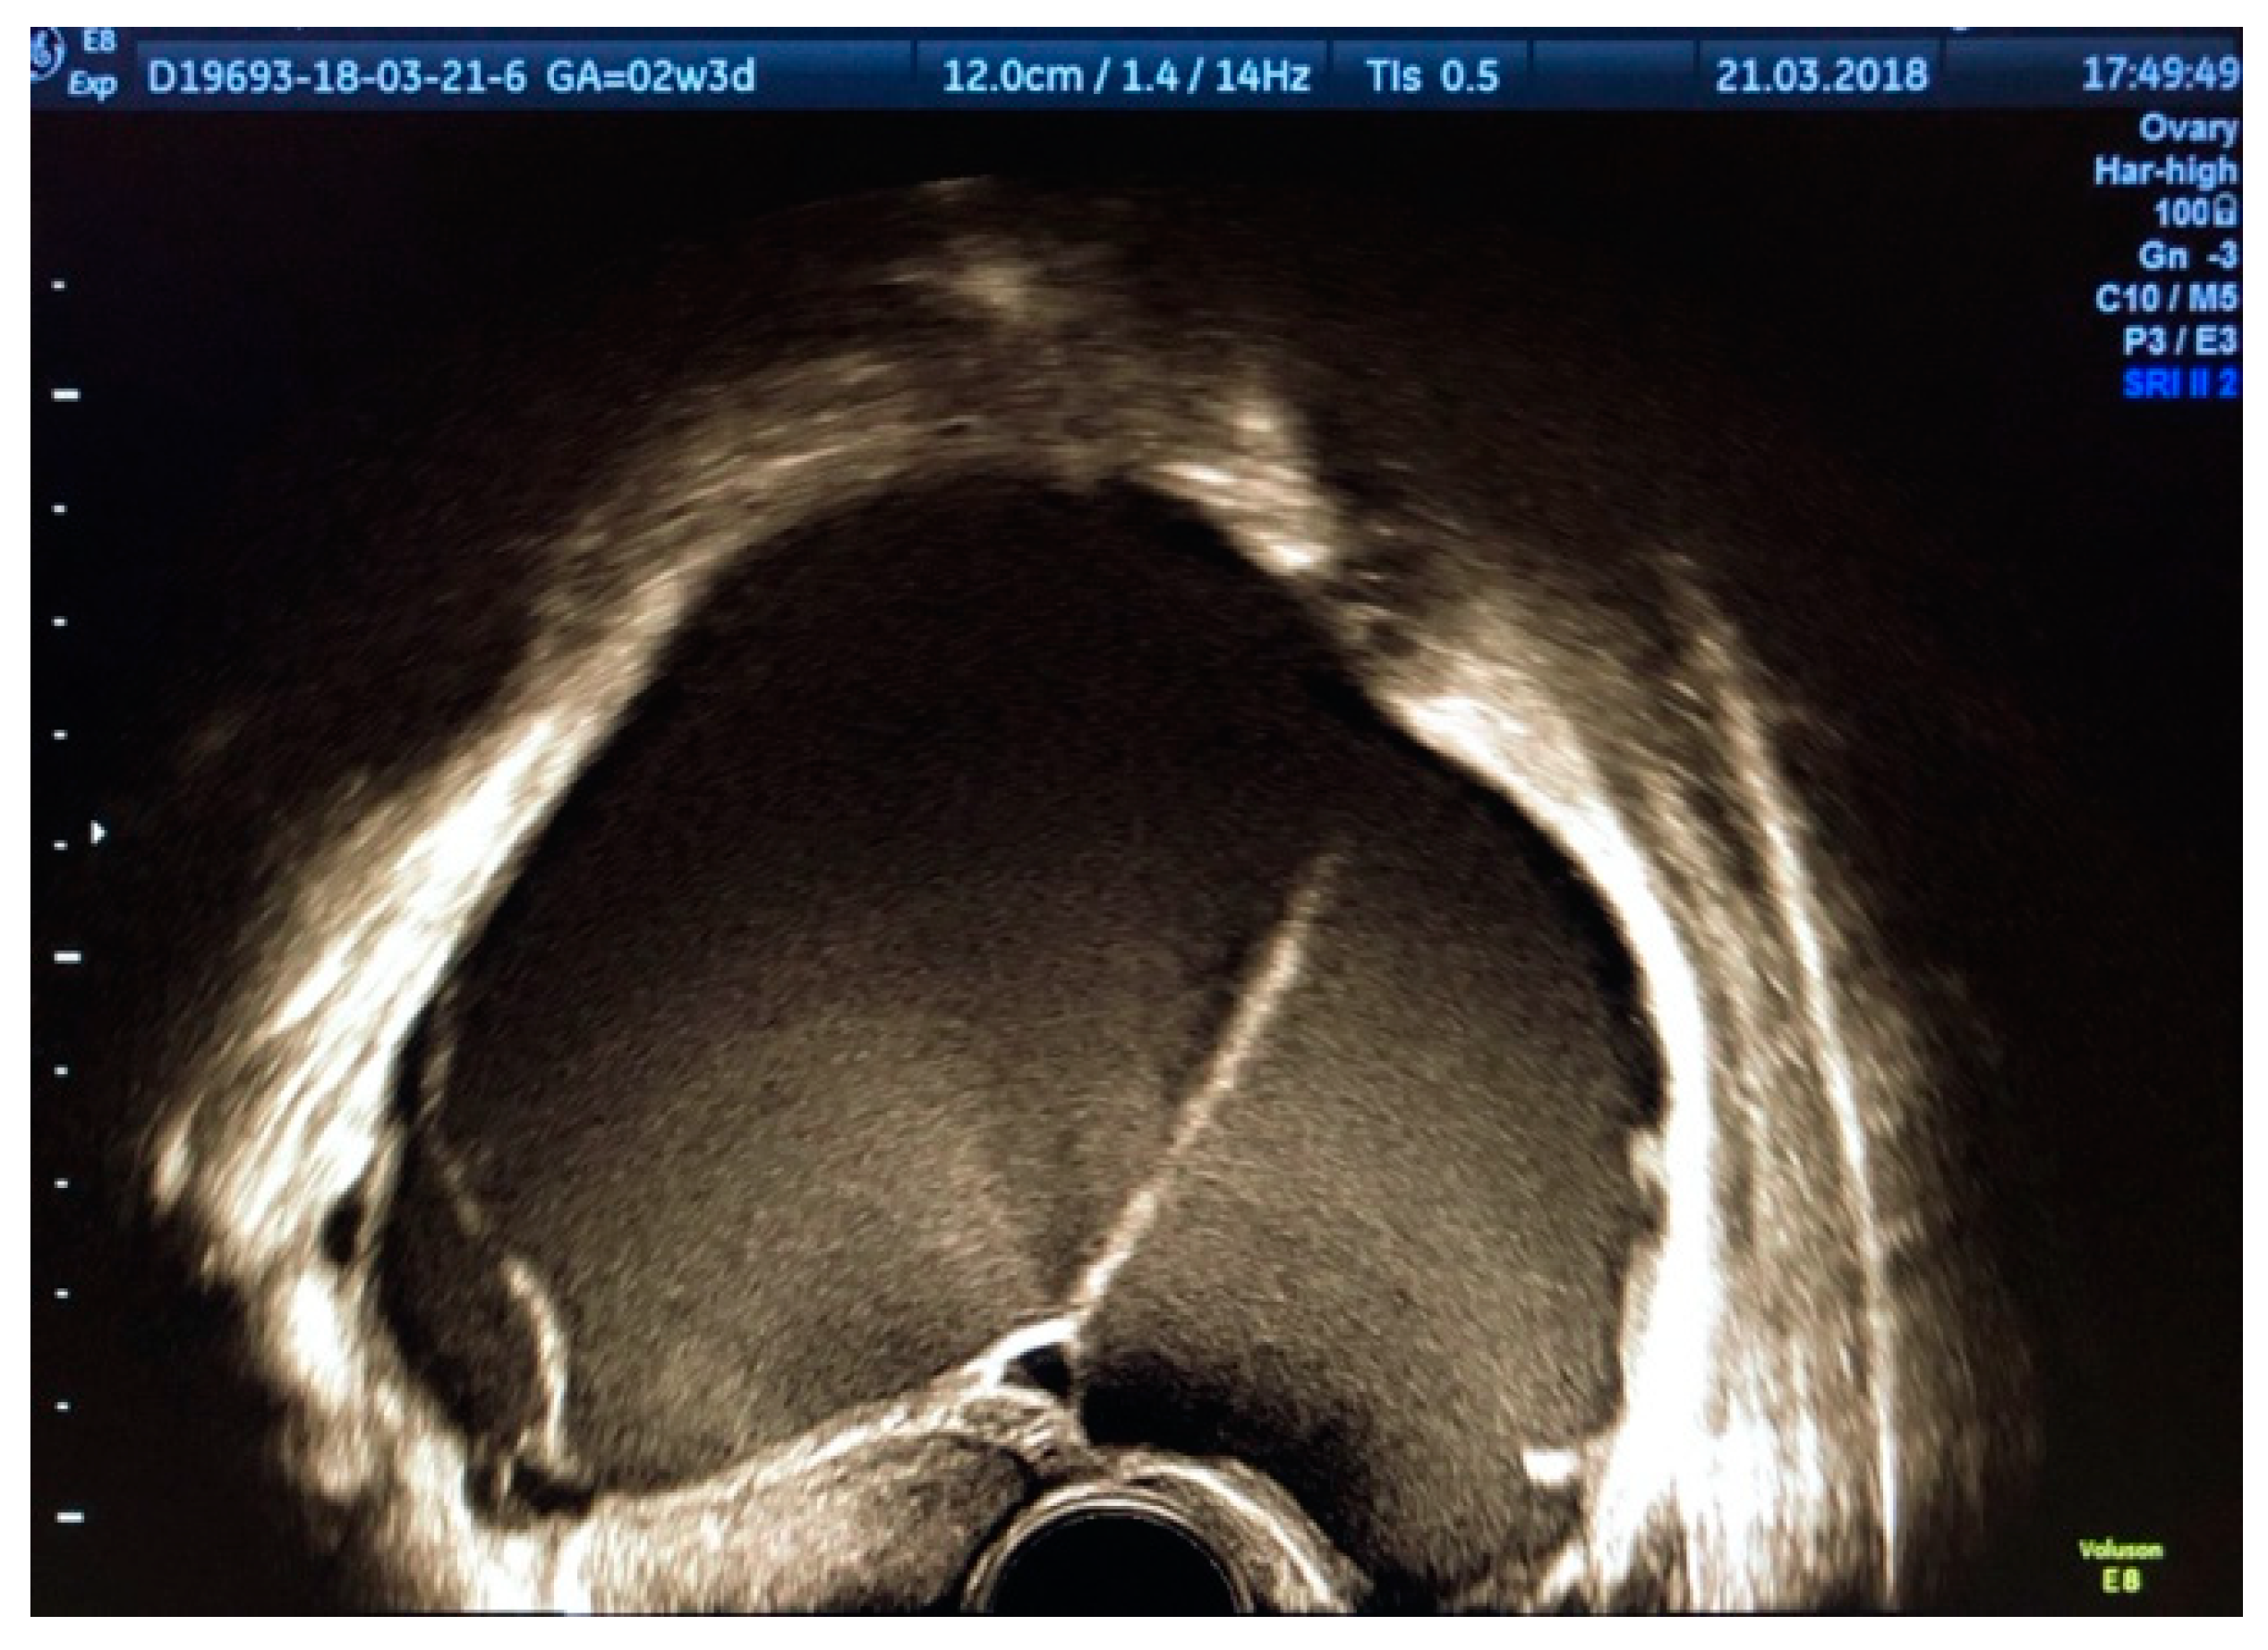

3.1. ADNEXA